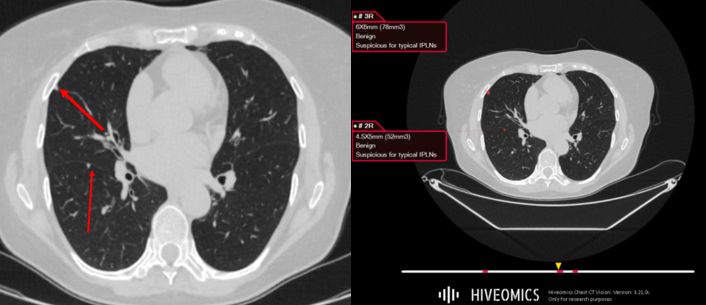

IPLN Model Illustration